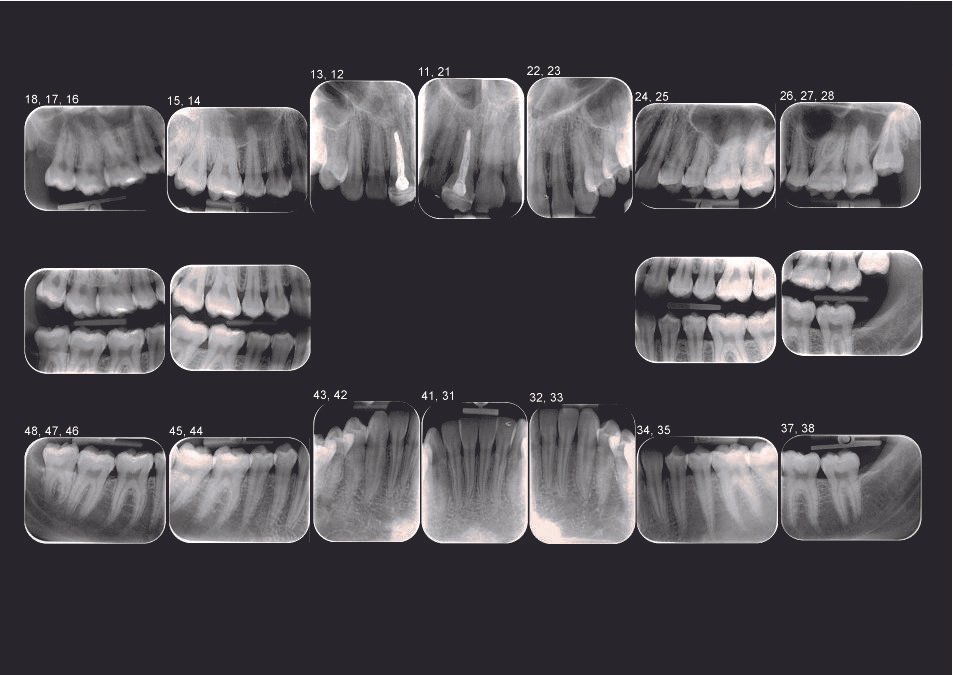

Status bi-maxilar

Radiografiile de status bi-maxilar sunt realizate separat pentru fiecare regiune a cavității bucale, oferind o imagine completă a acesteia. Acestea includ detalii precise ale grupelor de dinți, obținute prin tehnici retroalveolare și bitewing, pentru o evaluare amănunțită a structurilor dentare.

Radiografia digitală retroalveolară

Radiografia periapicală, cunoscută și sub denumirea de retroalveolară, este o investigație imagistică precisă, utilizată pentru a examina în detaliu un dinte sau un grup mic, de maximum doi-trei dinți. Aceasta surprinde întreaga structură a dintelui, la dimensiuni reale, incluzând coroana, rădăcina și osul alveolar în care dintele este fixat. Este o metodă indispensabilă în cadrul tratamentelor endodontice, parodontale sau chirurgicale, deoarece permite medicului stomatolog să evalueze cu acuratețe starea rădăcinii, a coroanei și a țesuturilor înconjurătoare. De asemenea, radiografia retroalveolară ajută la identificarea eventualelor afecțiuni, cum ar fi carii profunde, leziuni periapicale sau anomalii ale structurii dentare, contribuind astfel la un diagnostic corect și la planificarea unui tratament eficient.

Radiografia digitală bite-wing

Radiografia bitewing este utilizată pentru a analiza zonele de contact dintre coroanele dinților posteriori vecini sau pentru a evalua conturul osului alveolar în regiunea respectivă. Aceasta capturează simultan coroanele dinților superiori și inferiori pe aceeași imagine. Principalul său obiectiv este identificarea cariilor interdentare, precum și a celor ascunse sub plombe sau lucrări dentare, facilitând astfel un diagnostic precis pentru tratamentele stomatologice.